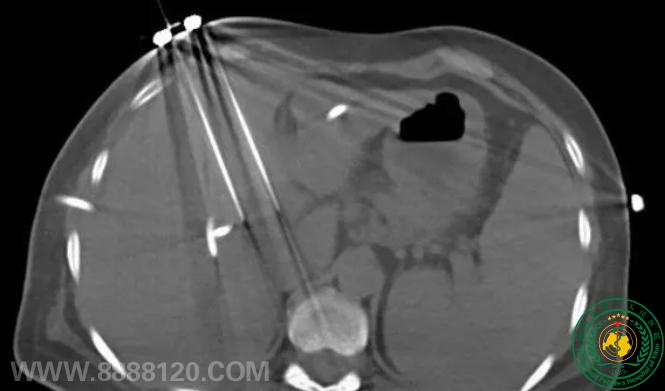

突破生命禁区!我院介入科成功完成川南首例、四川地市级医院首例经皮肝肿瘤纳米刀消融术,为肝门部恶性肿瘤患者带来新希望

突破生命禁区!我院介入科成功完成川南首例、四川地市级医院首例经皮肝肿瘤纳米刀消融术,为肝门部恶性肿瘤患者带来新希望62549